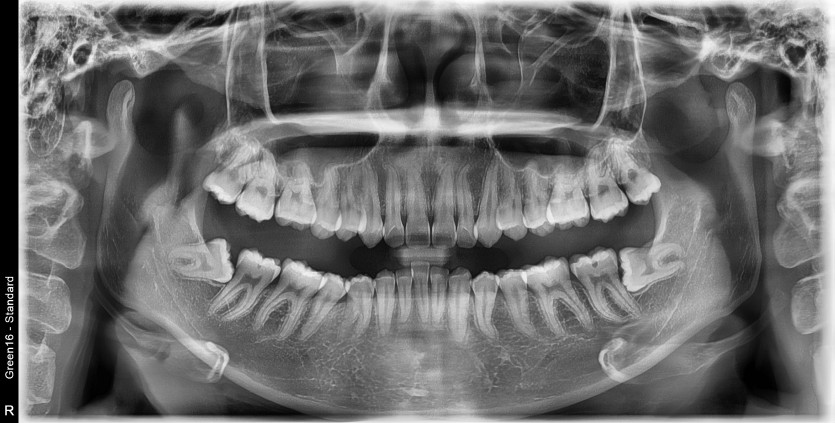

#18,48 사랑니 발치

구강 외과 전문의가 당일 발치했습니다.